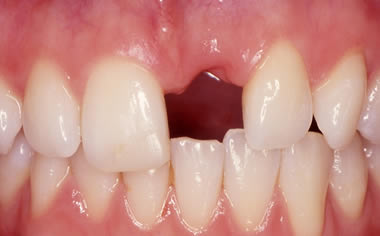

Missing upper front tooth replaced by dental implant and crown